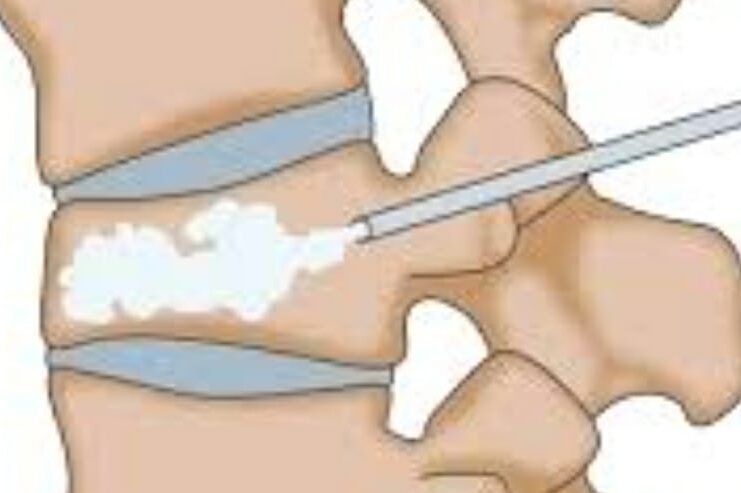

- Vertebroplasty